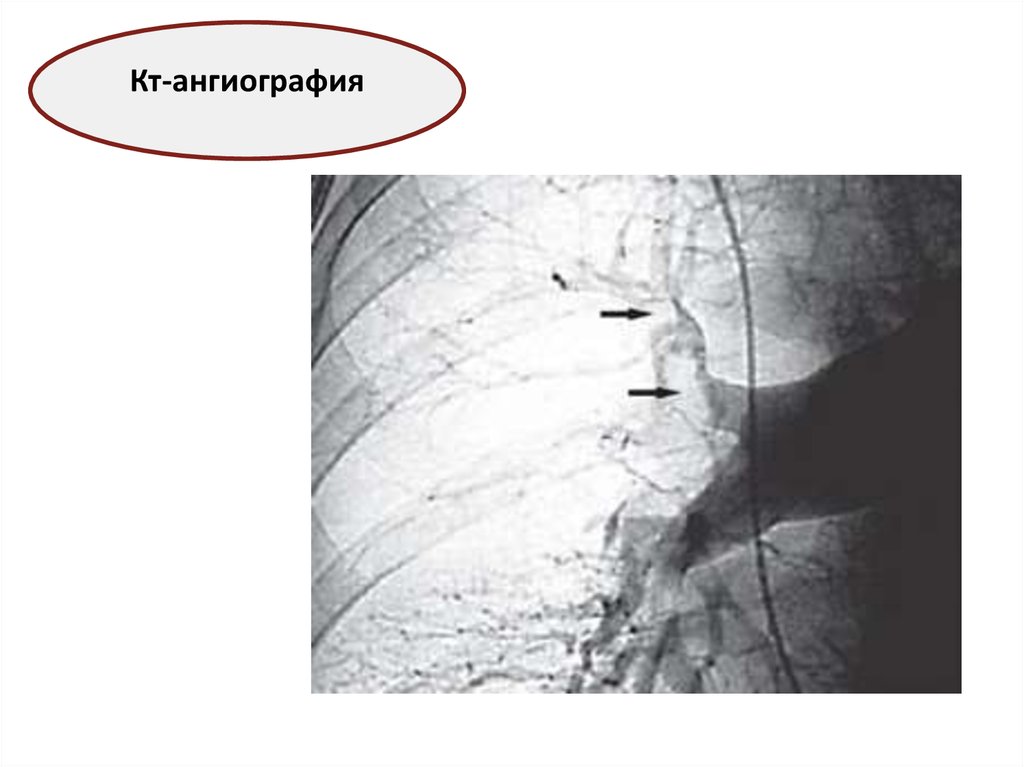

Кт-ангиография